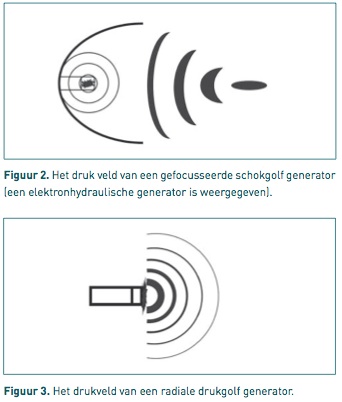

1) Gefocusseerd

Toestellen die gefocusseerde schokgolven produceren, deponeren de opgewekte energie op 1 punt (= focus). Hierdoor is de energie die toegediend wordt per mm3 veel groter dan bij een ESWT-toestel van het radiale type. De diepte van het 'focusgebied kan gekozen worden. Deze techniek is vergelijkbaar met de methode om nierstenen te verbrijzelen.

Er zijn drie manieren om gefocusseerde schokgolven voor ESWT op te wekken:

- Elektro-hydraulisch (EH): Een vonk springt over tussen twee elektroden in een waterbad (in de behandelkop). Hierdoor verdampt het water rond de elektroden en ontstaat een gasbel. Deze gasbel zet uit en implodeert waardoor een schokgolf ontstaat. Door middel van een elliptische spiegel worden de schokgolven gefocust.